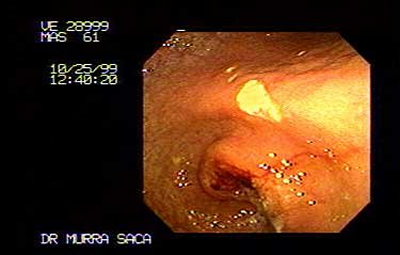

Paciente Masculino de 51 Años:

Hermano de prestigioso Cirujano Pediatra de El Salvador. El cual me solicita que le practique este estudio, le diagnosticamos este carcinoma obstructivo, la imagen endoscópica de control, Fue después de un año de habérsele diagnosticado por lo que Se le había practicado una derivación en omhmeda por haber sido irresecable al intento quirúrgico es de notar que esta imagen endoscópica es después de haber recibido quimioterapia y radiaciones con Cobalto.